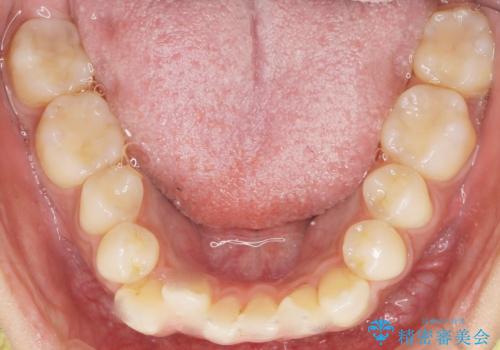

- 奥歯にフロスを通すとにおいがすることを気にされ、来院された患者様です。

精査したところ、奥歯に充填された保険内のコンポジットレジンの適合が悪いことにより、汚れがたまりやすい状態でした。

不適合なレジンを除去し、セラミックインレーによる治療を行いました。(右上76左上67右下7の計5本)

気にされていたフロスをした時のにおいがなくなり、喜んで頂けました。

治療終了後半年のメンテナンス時には「咬み合わせもばっちりです!」とおっしゃって下さいました。